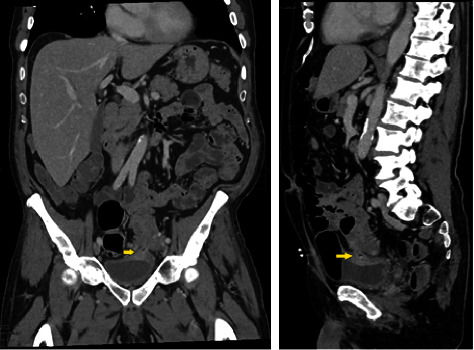

Colovesical fistula is an infrequent complication of diverticular disease that presents with pneumaturia, fecaluria, dysuria and, rarely, hematuria or hematochezia. Here we present a case of concurrent hematuria and rectal bleeding arising from a diverticular bleed traversing a previously undiagnosed colovesical fistula. Other causes of colovesical fistula include Crohn's disease, radiation, and malignancy, though it is most commonly caused by complicated diverticulitis as in this case. Computed tomography (CT) imaging, cystoscopy, and gastrograffin enema have been described as high-yield diagnostic tests. Interestingly, colonoscopy is only successful in diagnosing colovesical fistula in approximately 55% of cases. Management often requires surgical intervention, as in this case, given limited success with conservative management. Colovesical fistula should be considered in patients presenting with fecaluria, pneumaturia, and dysuria as well as in cases of hematuria.